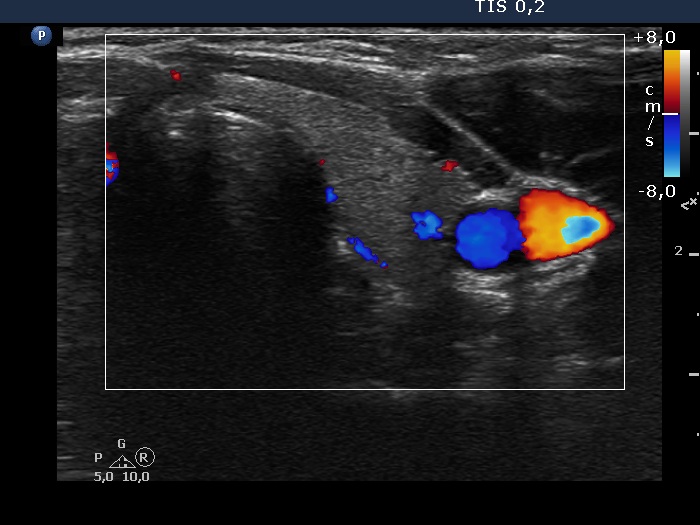

Thyroid cancers - case 327 (ultrasonographic picture 6)

Left lobe, transverse scan, color Doppler mode.